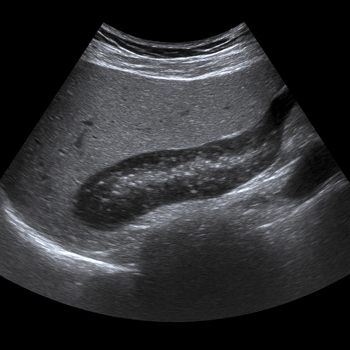

Ultrasound Pancreas

• Ultrasound of the pancreas shows inflammation, cysts, stones and structural changes in the pancreas.

• Recommended for abdominal pain, jaundice or elevated enzyme values.

• Quick, painless and radiation-free examination of the pancreas.

• Written opinion and recommendation from a specialist doctor are included.